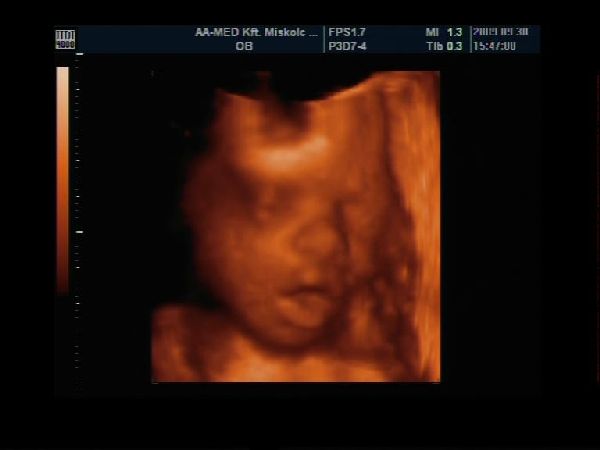

28. heti Uh Kép

Kép